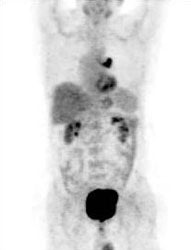

Unsuspected bone metastases: The patient shown below had a cavitary left lung non-small cell lung cancer. There was no uptake of tracer within the aortopulmonary window lymph nodes detected on CT to suggest metastases, however, unsuspected bone metastases were found in the left anterior 4th rib (black arrow) and lumbar spine (red arrows- not included in staging lung CT scan). The presence of bone metastases significantly alters patient prognosis and management. PET imaging provides a rapid whole body survey for the detection of unsuspected metastatic disease. |